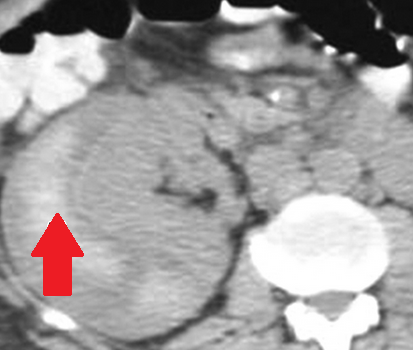

Αυτόματη ρήξη/αιμορραγία νεφρού — νεφροκυτταρικό καρκίνωμα (Ευγενική παραχώρηση Dr. V. Penopoulos)